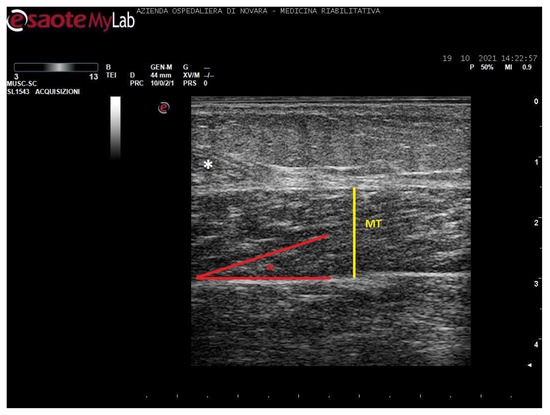

We acquired images of the medial gastrocnemius (MG) and soleus (SOL). Images were processed through the software ImageJ (National Institutes of Health, USA) in order to measure the muscle thickness (MT, cm), the cross-sectional area (CSA, cm2), the pennation angle (α, °), and the mean gray value (MGV, range 0-255). MGV was assessed considering the whole muscle longitudinal section as region of interest (ROI). The gray scale spreads from 0 (black) to 255 (white).

Measurements were taken as shown in Figure 1, Figure 2, Figure 3 and Figure 4.

Figure 2. Ultrasound image of medial gastrocnemius in longitudinal section. In yellow: muscle thickness (MT), in red: pennation angle (α).